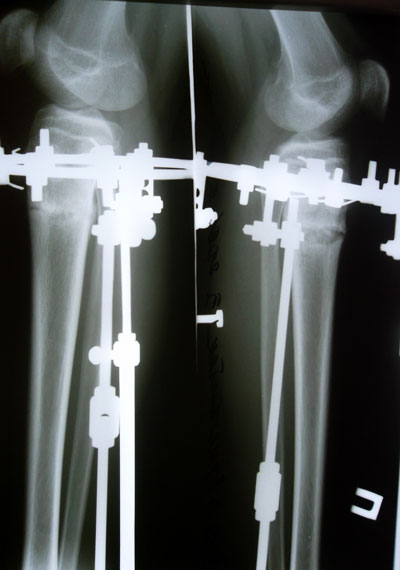

Дата операции 27.05.2014г.

Дата снятия аппаратов 22.07.2014г.

Срок лечения 55 дней.